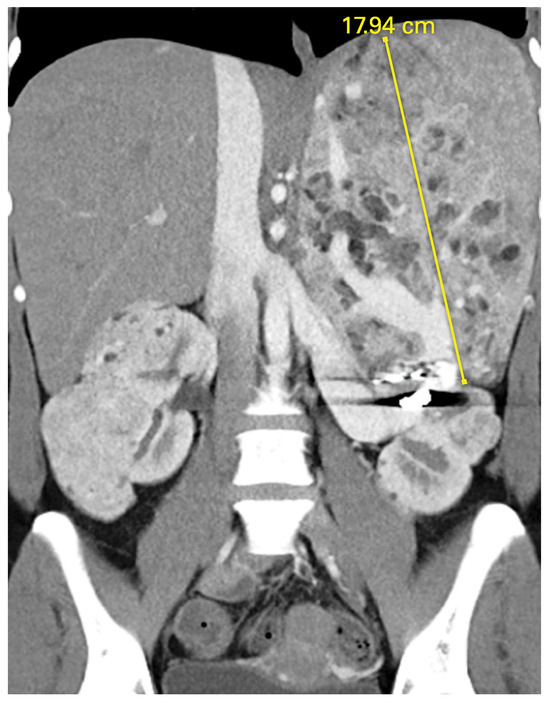

Figure 2.

Epithelioid variant angiomyolipoma (AML) in a patient with tuberous sclerosis complex (TSC) who had failed two attempts at angioembolization of large vessel (coil seen).

AMLs (mesenchymal tumors of the PEComa family) are typically bilateral and multifocal. They develop in late childhood at a median age of 16.9 years [65]. Bulky AMLs may merge, making it difficult to distinguish clear boundaries between lesions. The majority are benign, consisting of vascular, smooth muscle, and fatty elements. A rare but important variant, epithelioid AML, is composed of epithelioid cells with minimal to no fat. Epithelioid AMLs may grow rapidly and are more prone to necrosis and hemorrhage and progression, with distant metastases observed in up to 33% in multiple series (Figure 2). Screening recommendations include baseline abdominal imaging with CT or MRI at diagnosis and then every 1 to 3 years [66]. AMLs are usually easily identified by the presence of macroscopic fat, though fat-poor lesions may require confirmatory biopsy. Ultrasound does not adequately assess tumor size or presence of fat. Contrast-enhanced MRI should be coordinated with brain MRI whenever possible to minimize number of procedures under sedation. With prospective surveillance, more than 80% of TSC AMLs are identified prior to onset of symptoms or hemorrhage [65]. They can be safely observed until they reach 4 cm, at which time embolization or resection is indicated. Epithelioid variants should be considered for earlier resection given their risk for malignant behavior. Alternatively, everolimus is approved for the medical management of AML and has also shown efficacy in the setting of metastatic epithelioid AML [67].